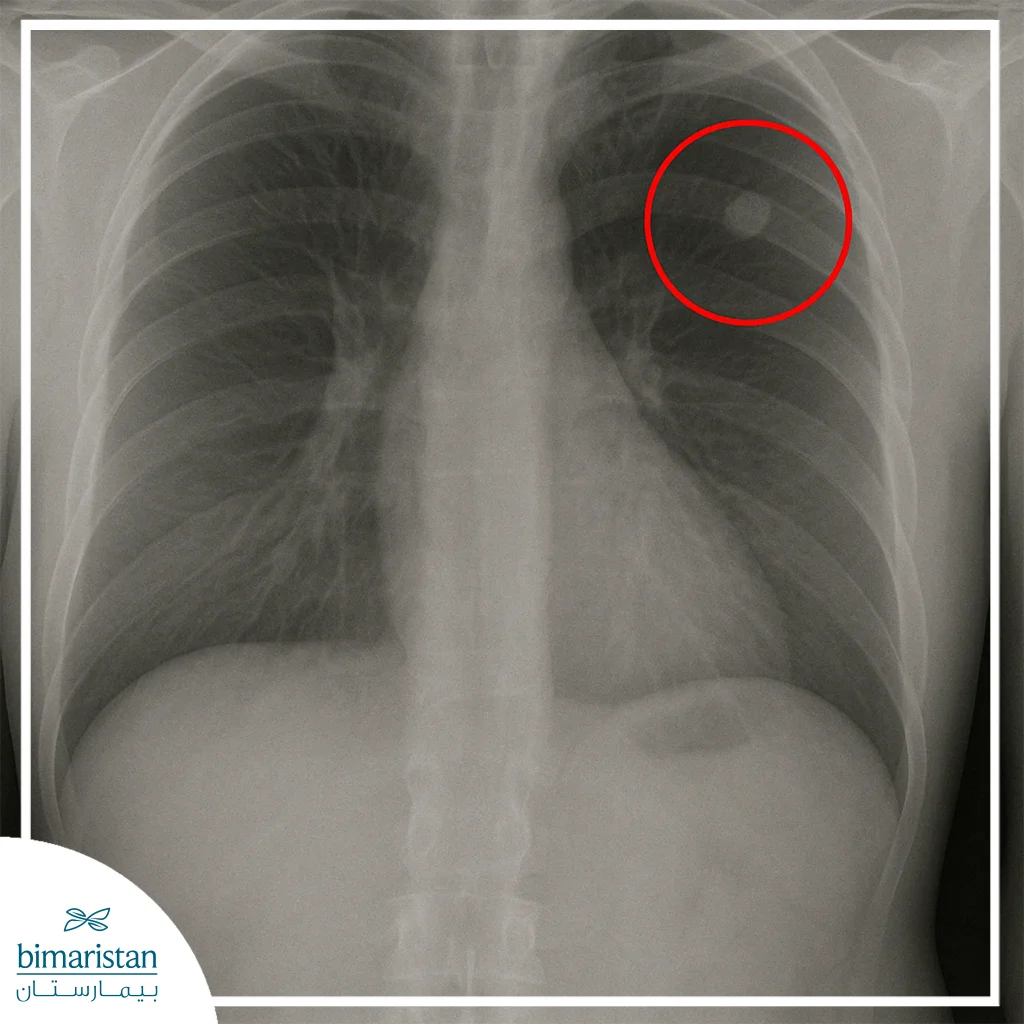

تُعرَّف العقيدات الرئوية بأنها مناطق صغيرة مستديرة أو بيضوية الشكل تظهر داخل نسيج الرئة، وتُشاهد عادة في صور الصدر الشعاعية أو في التصوير المقطعي المحوسب على شكل بقع بيضاء مميزة تختلف عن النسيج الرئوي الطبيعي المحيط بها، ويُطلق عليها أحياناً اسم “عقيدات الرئة” أو “النقاط الرئوية”، ويُعدّ أي تكوّن لا يتجاوز قطره ثلاثة سنتيمترات ضمن نطاق العقيدات، في حين يُصنَف ما هو أكبر من ذلك ككتلة رئوية.

غالباً ما تُكتشف العقيدات الرئوية بالصدفة أثناء إجراء تصوير للصدر بهدف آخر، كالفحص الشعاعي الروتيني أو التصوير المقطعي منخفض الجرعة المستخدم في برامج الكشف المبكر عن سرطان الرئة، وبعد اكتشافها يبدأ الطبيب بتقييم خصائصها من حيث الحجم والشكل وحدود العقيدة وكثافتها لتحديد مدى الحاجة إلى فحوص إضافية.

يُعتبر التصوير المقطعي المحوسب الوسيلة الأدق في تشخيص هذه العقيدات، إذ يُظهر تفاصيل دقيقة للبنية الداخلية ويسمح بمقارنة حجمها مع صور سابقة لتحديد ما إذا كانت مستقرة أو متزايدة. غالباً ما تُعدّ العقيدات الصغيرة ذات الحواف الملساء أقل خطورة، لذلك يُكتفى بمراقبتها دورياً عبر التصوير دون تدخل فوري. أما العقيدات التي تُظهر صفات غير طبيعية أو تغيّراً في حجمها بمرور الوقت، فتحتاج إلى استقصاءات إضافية تشمل فحوص الدم والبلغم للتحري عن الالتهابات أو العدوى المزمنة، أو إجراء تصوير متقدم لتقييم نشاط الخلايا داخلها وتقدير احتمال الخباثة.

يُشكّل عدد العقيدات التي تظهر في الرئة عاملاً مهماً في تقييم سببها واحتمال خطورتها، فالعقيدة المفردة هي تغيّر موضعي واحد في نسيج الرئة، وغالباً ما تكون ناجمة عن سبب محدد كالتهاب قديم أو ورم حميد، ويُركّز الطبيب في هذه الحالة على تحليل شكل العقيدة وحدودها وتطورها الزمني لتحديد ما إذا كانت تحتاج إلى متابعة أو خزعة.